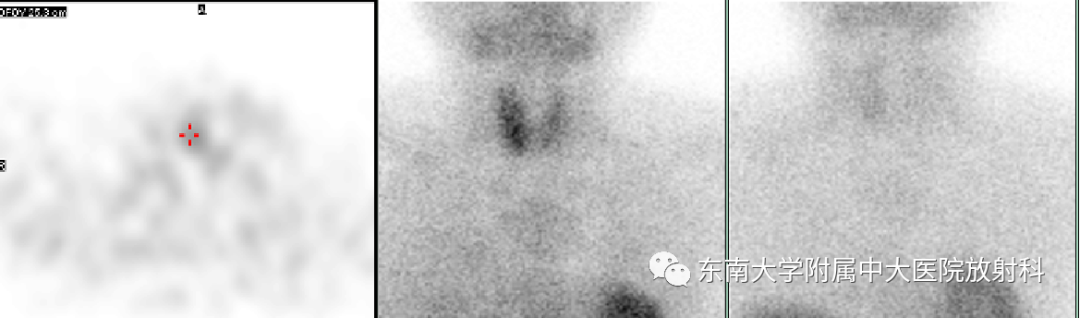

主诉:骨痛2月余,发现血钙升高6天

既往史:2月余前无明显诱因出现右髋痛、腰痛。6天前查血钙3.97mmol/L ,外院检查,全身多处骨质破坏,考虑恶性病变,穿刺结果不详

辅助检查:钙:3.84mmol/L , 甲状旁腺素421.55pg/mL ,超声探查:右侧甲状旁腺区见大小约高回声团